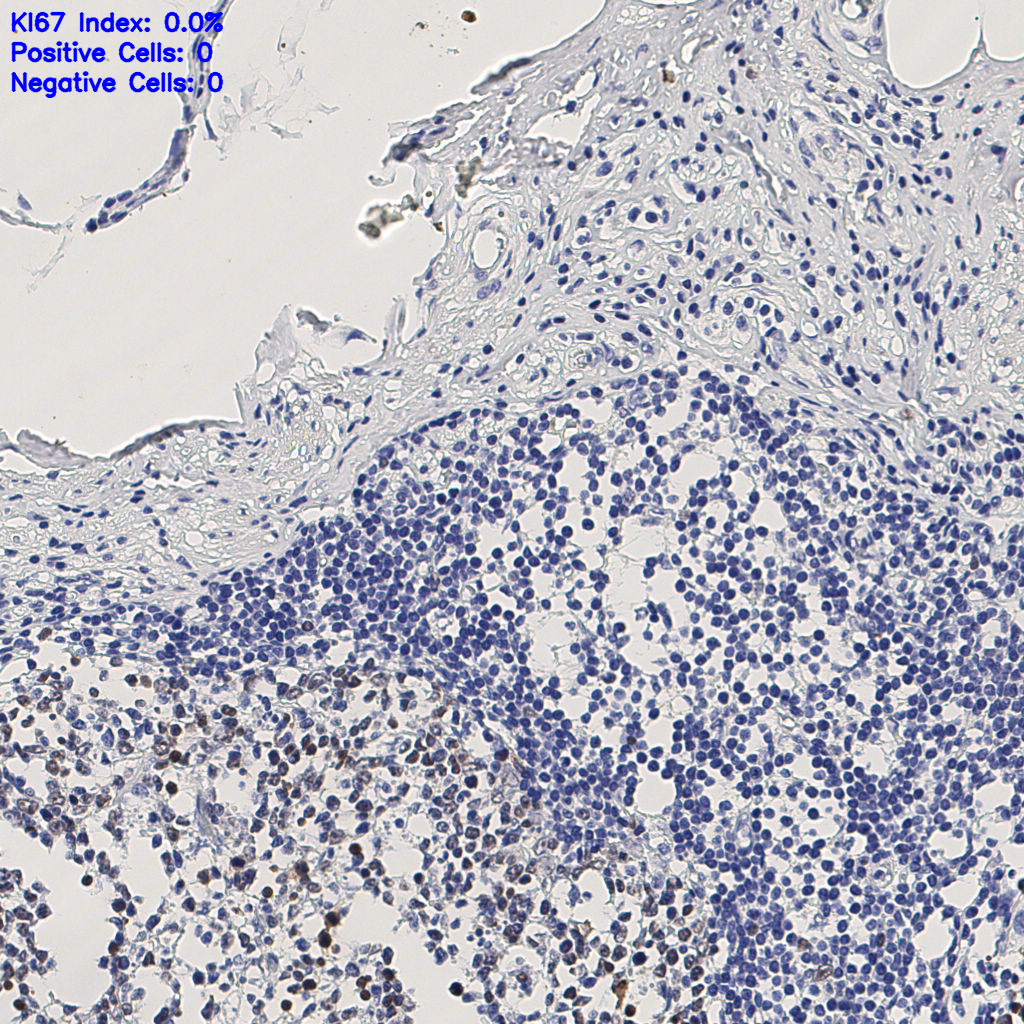

7.85%

Ki67 指数

阴 1104

阳 94

缩略图

标记后

标记前